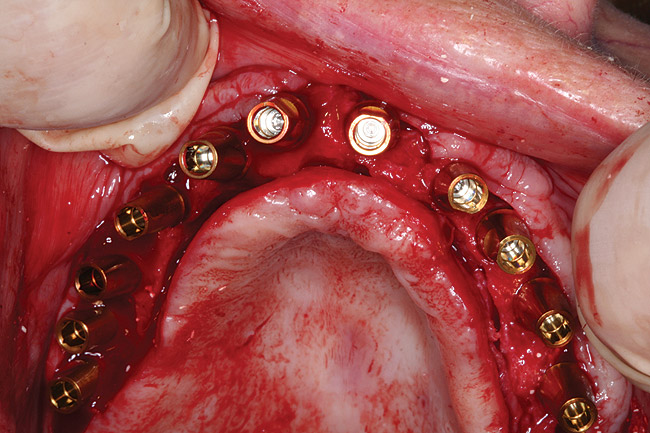

After 6 months of healing, a CBCT scan was taken and good bone formation was seen on the axial (Figure 18) and panograph (Figure 19) views. The CBCT was then used to plan for placement of dental implants (Figure 20). Upon full-thickness reflection of the ridge, abundant bone contour was observed. Internal hex dental implants (BioHorizons) were placed according to the locations planned on the CBCT (Figure 21). After a healing period of 4 months, the implants were uncovered (Figure 22) and abutments were placed (Figure 23). A panograph taken 1 year after this stage revealed the final restorations on well-integrated implants (Figure 24). The patient’s smile reveals a fixed prosthesis that simulates her natural teeth (Figure 25).

Figure 21  Clinical view of implant placement 6 months post-graft healing.

Figure 21